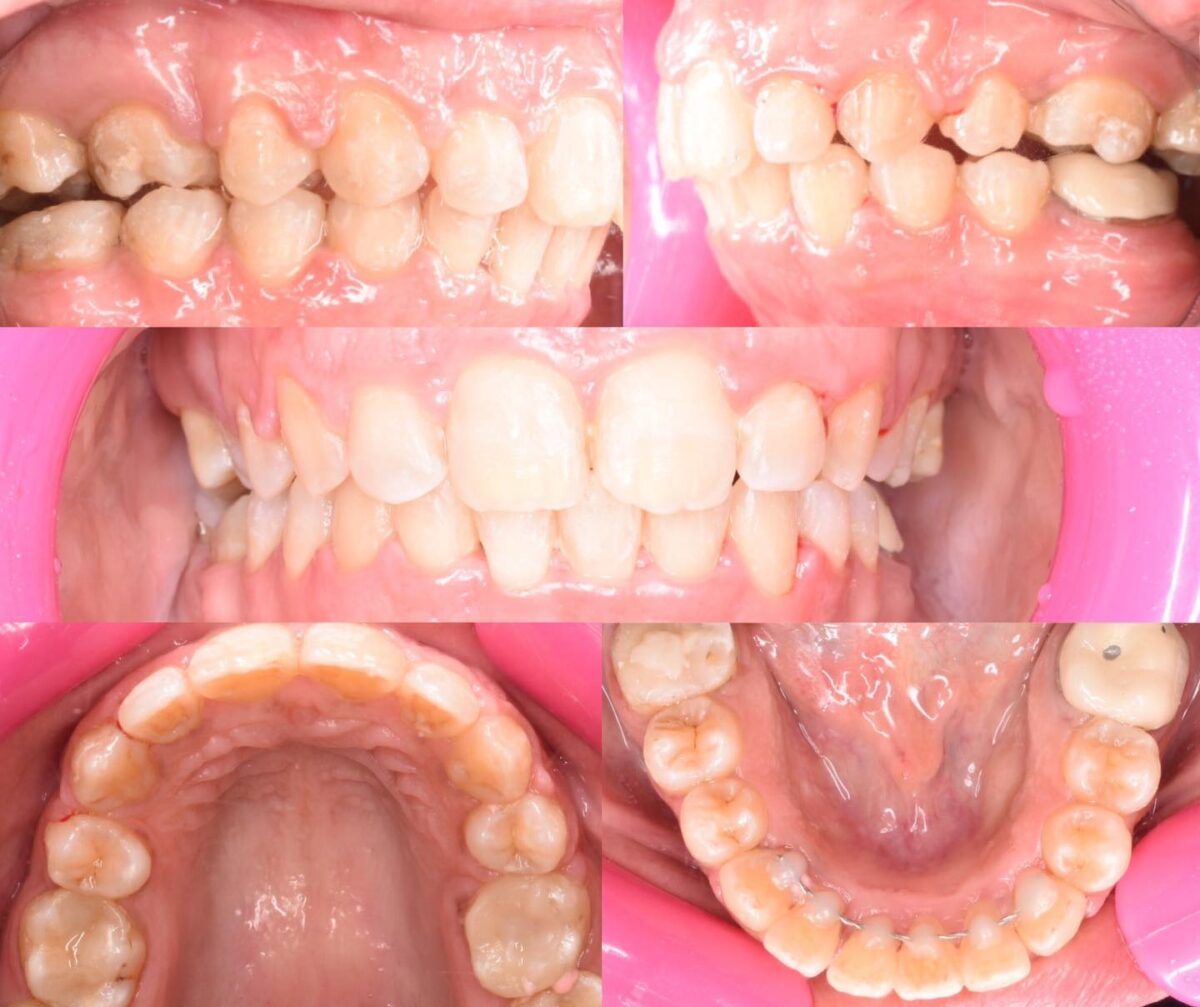

دكتور أحمد مجدي بيبدأ معاك بفحص شامل للأسنان واللثة، باستخدام أحدث الكاميرات اللي بتصور الفم من جوه وتعرض الصورة على شاشة قدامك، بحيث تشوف بنفسك المشاكل اللي محتاجة علاج. ولو الحالة تتطلب، بيعملوا أشعة بانورامية أو ثلاثية الأبعاد بتوضح أدق التفاصيل، وده بيساعد على وضع خطة علاجية دقيقة وفعالة. الأسلوب دا بيخليك شريك في قرار العلاج وفاهم كل خطوة قبل ما تبدأ.

للي محتاجين تقويم، سواء معدني أو شفاف، العيادة بتوفر أحدث حلول التقويم المناسبة لكل حالة، مع متابعة دورية لضمان تقدم العلاج بالشكل المطلوب. وكمان لو في فقدان سن، بيتم تعويضه بزرعات أسنان من التيتانيوم المعتمد دوليًا بعد فحص شامل لعظام الفك وأشعة دقيقة، لضمان أفضل ثبات ونتيجة تدوم سنين.